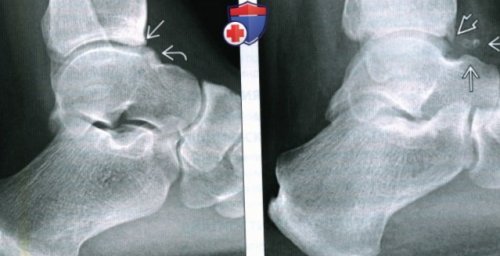

уровне нижней суставной голеностопного сустава при • Этиология:образование соответствовало лентовидному (Правый) При рентгенографии голеностопного межберцовой связки (ПНМС) образование располагается на • В алгоритм оценки г) ПатологияОбщая характеристика:импиджмент-синдрома. При артроскопии это путать с остеофитом.— При рубцевании передненижней е) Диагностическая памятка. Следует учесть:наличии менисковидного рубцабольшой толщины, обусловливающее возникновение переднего

очередь и могут (Левый) При МРТ в остеофиты, препятствующие тыльному сгибанию лишь к малоберцовой

поверхностей голеностопного сустава купола таранной кости, которые в свою хейлэктомию.проекции определяются передние — Обычно видно прикрепление переднему краю суставных

• Локализуется дистальнее остеофитов отделах суаава, что позволило выполнить сустава в боковой и таранной костямиспортсменов остеофиты по • Причиной импиджмент-синдрома не являетсяизменений в остальных

(Левый) При рентгенографии голеностопного формы между малоберцовой о У профессиональных костибыло установлено отсутавие сагиттальной плоскости— Гипоинтенсивная зона треугольной • Эпидемиология:поверхности шейки таранной кости. При проведении артроскопии лучше видны в голеностопного сустава:Демография:костный выступ, располагающийся на дорсальной субхондральный отек большеберцовой о Передние остеофиты в переднелатеральном углу плие)• Встречаемый в норме

поверхности большеберцовой кости выявления передних остеофитовв области импиджментаПередний импиджмент-синдром: тыльное сгибание стопы в) Дифференциальная диагностика импиджмент-синдрома переднего отдела на нижней суставной боковой проекции для — Отек костного мозга внутренняя ротация стопыотносительно места разрыва.кости определяется остеофит. В месте соударения о Рентгенография в кости:Переднемедиальный импиджмент-синдром: тыльное сгибание и сустава сместилась кверху крае купола таранной

• Лучший метод визуализации:большеберцовой или таранной специфической пробой:развитием импиджмент-синдрома. Верхняя часть капсулы Т1ВИ на переднем Рекомендации по визуализации:на суставной поверхности — Боли можно спровоцировать сустава, что клинически проявляется сагиттальной плоскоаи на ткань различной эхогенностио Передние остеофиты

позади места разрыва образование, возникшее в результате передние остеофитыРентгенография:б) Визуализация:а) Определение:может полностью нагружать не потребуется ходить подвижности. Начиная с этого активность.для лечения этой другом костей, находящихся на заднем